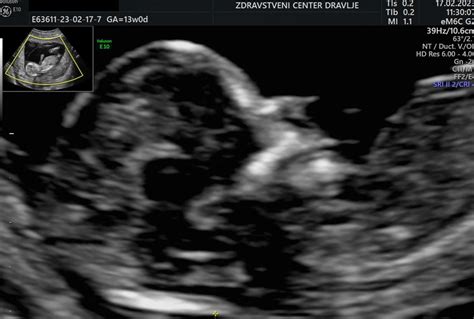

Nuhalna svetlina in zgodnja diagnostika nosečnosti

Nuhalna (tilnična) svetlina je tekočina, nabrana pod kožo v zatilju nerojenega otroka. Območje na ultrazvočni sliki je zaradi te tekočine svetlejše od okolice, od tod tudi ime "svetlina". Nuhalna svetlina se pri plodu pojavi med 11. in 14. tednom nosečnosti. V tem obdobju se mezgovni sistem in ledvice še razvijajo, kar lahko povzroči začasno nabiranje tekočine. Ko se mezgovni sistem popolnoma razvije, svetlina običajno izgine.

Merjenje nuhalne svetline je postalo pomembna metoda predrojstvene diagnostike. Z ultrazvokom lahko v nuhalni svetlini opazimo določene nepravilnosti, ki lahko kažejo na genetske abnormalnosti, kot so srčne anomalije ali Downov sindrom. Pomembno je poudariti, da je merjenje nuhalne svetline presejalni poskus in ne diagnostična metoda. To pomeni, da obstaja možnost lažno negativnih (preiskava ne pokaže anomalije, čeprav obstaja) ali lažno pozitivnih izidov (preiskava pokaže na anomalijo, čeprav je plod zdrav).

Pri plodu med 11. in 14. tednom nosečnosti je povprečna velikost nuhalne svetline med 1-2,5 mm. Statistično je kromosomska mutacija prisotna pri približno 2 od 10 otrok z nuhalno svetlino, večjo od 3,0 mm. Nekateri zdravniki priporočajo dodatne genetske analize, če je nuhalna svetlina večja od 2,5 mm, še posebej zaradi možnosti lažnih negativnih izidov.

Preiskava nuhalne svetline se ne opravi pri vseh nosečnicah, temveč se lahko nosečnica zanjo prostovoljno odloči. V Sloveniji je ta preiskava za nosečnico brezplačna.

Prvi pregled nosečnice se opravi med 8. in 12. tednom nosečnosti, kjer se nosečnost potrdi, določi stopnja ogroženosti nosečnice in ploda ter izračuna predvideni datum poroda (PDP). Na prvem pregledu se opravi tudi ultrazvočni pregled, ki omogoča oceno stanja ploda, določitev števila plodov, ugotavljanje vitalnosti in gestacijske starosti.

Nosečnost delimo na tri trimesečja. V prvem trimesečju (do 12. tedna) je največja nevarnost spontanega splava. V tem obdobju se poleg osnovnih pregledov (teža, krvni tlak, pregled urina, pregled materničnega vratu) priporočajo tudi dodatne preiskave, kot je merjenje nuhalne svetline in kariotipizacija (npr. horionska biopsija), še posebej za nosečnice, starejše od 35 let.